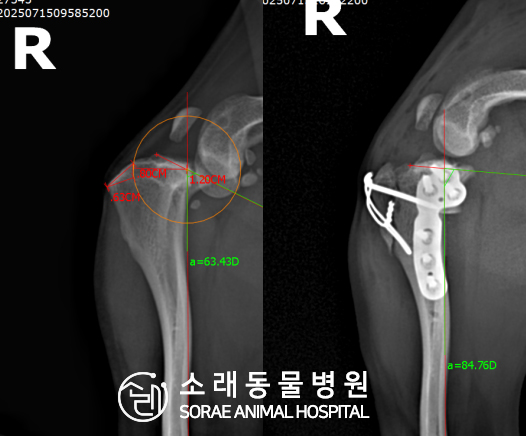

계산식으로 사전에 계획해두었던 플랜에 따라 경골을 절제하고

플레이트와 스크류를 사용하여 임플란트를 적용해 주었습니다.

반대 방향으로 밀려나 어긋나있던 대퇴골과 정강이가

제 자리를 찾으면서 무릎의 각도가 교정된 것을 확인할 수 있습니다